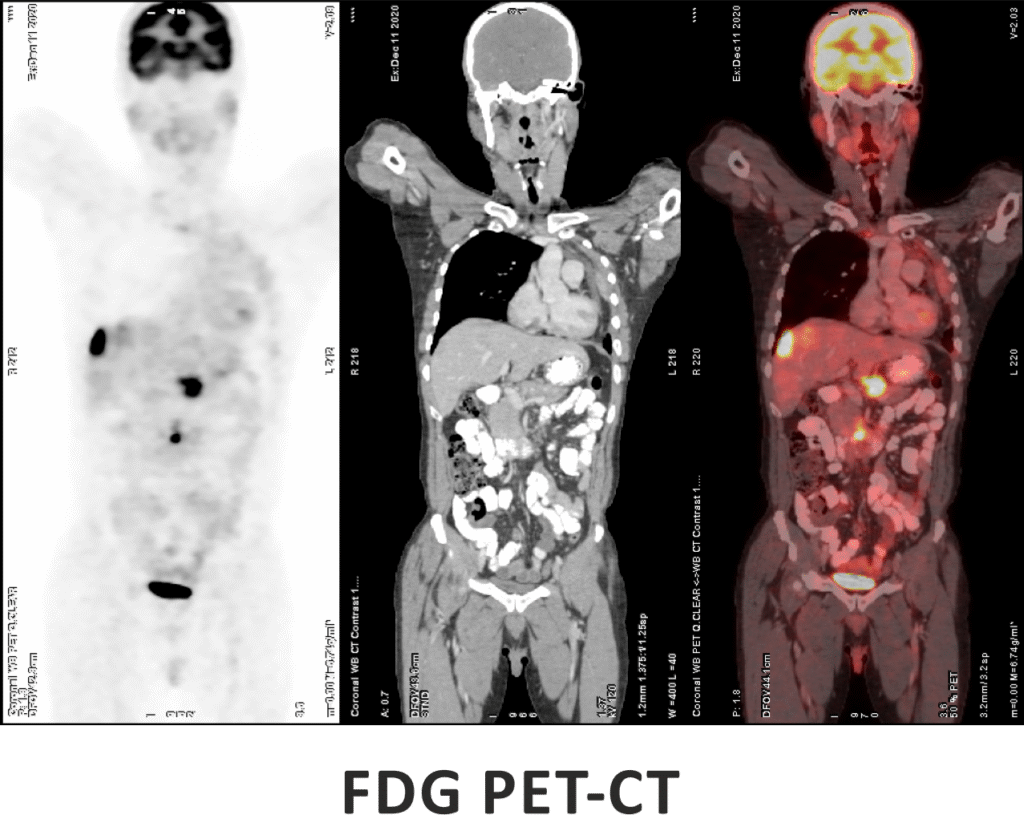

FDG PET-CT is one of the most advanced and widely used imaging techniques in modern medicine, especially for cancer evaluation. It works by detecting areas of increased glucose metabolism in the body, which is a common characteristic of active cancer cells, infections, and certain inflammatory conditions. By combining the metabolic insights from PET with the anatomical detail of CT, FDG PET-CT offers exceptional accuracy in locating and characterizing disease.

This scan plays a critical role in the diagnosis, staging, and treatment planning of a wide range of cancers. It also helps assess how well a tumor is responding to therapy and can detect recurrence at an early stage, often before it becomes visible on conventional scans.

Key Applications:

- Initial staging of various cancers (lung, breast, lymphoma, etc.)

- Monitoring treatment response

- Detecting tumor recurrence or metastasis

- Whole-body oncological assessment